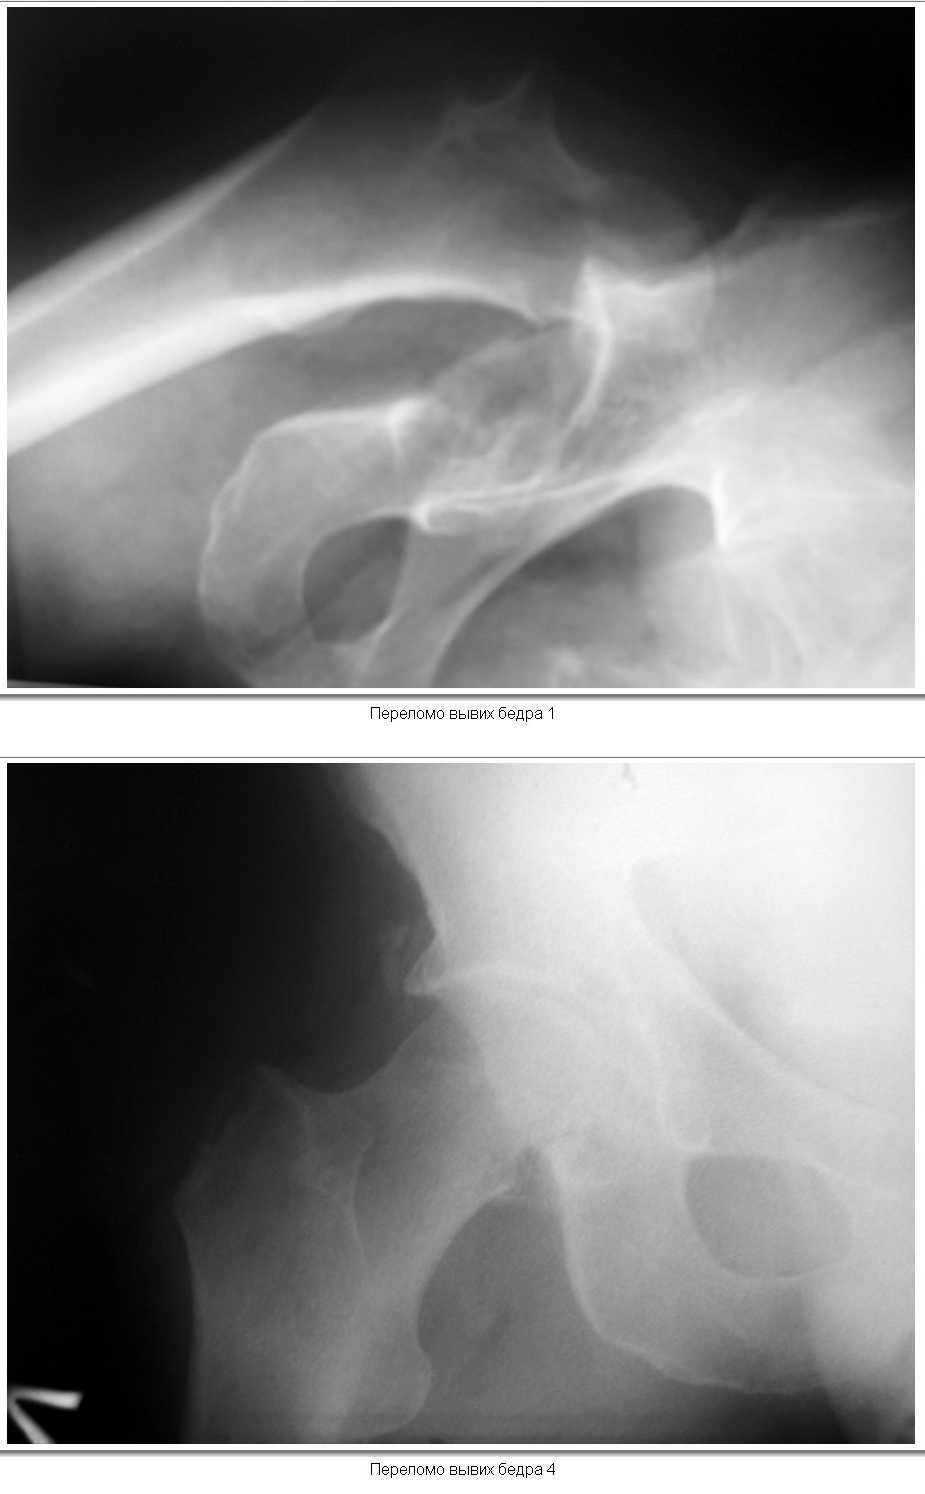

Здравствуйте, уважаемые коллеги.Хотел бы посоветоваться с Вами по тактике лечения одного из наших пациентов. 12.02.2008 г. поступил пациент,мужчина, 50 лет.В результате удара бревном получил закрытый вывих левого бедра и переломом нижнего фрагмента головки( тип 1 по Pipkin). При поступлении вывих вправлен,налажено скелетное вытяжение за н\3 бедра. На контрольной рентгенограмме фрагмент головки располагается вне полости сустава, в подвздошной области. Хотелось бы узнать ваше мнение о необходимости оперативного лечения(Фиксации перелома головки)и его технических особенностей(способ фиксации). КТ выполнить временно невозможно (поломка аппарата).

По представленным снимкам повреждений вертлужной впадины не видно. Фрагмент головки мелкий находится вне нагружаемой зоны.

Синтез такого фрагмента не целесообразен, т.к. он не приживется и он не участвует в стабилизации головки под сводом.

Если при движениях он не мешает - оставте его в покое. Пусть полежит на вытяжении 3-4 недели

Если имеется четкое ограничение движений (что маловероятно) надо отломок удалить.